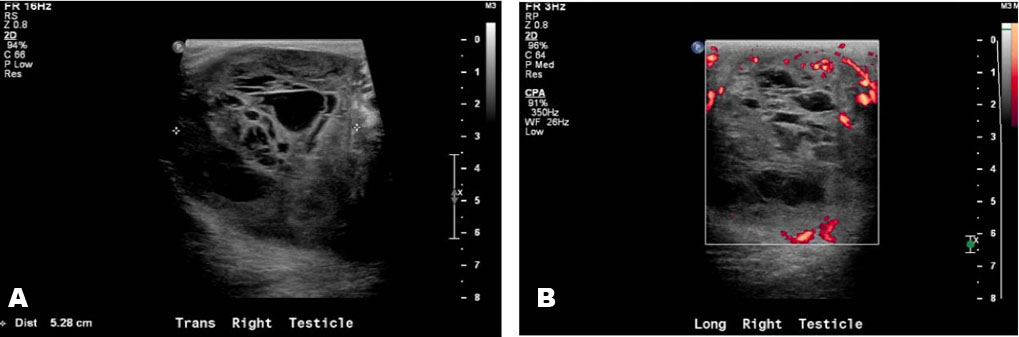

Systemic amyloidosis causing profound retroperitoneal and perinephric calcified deposits

Keywords: Amyloidosis, Lymphoplasmacytic lymphoma, Retroperitoneal calcifications, Systemic amyloidosis